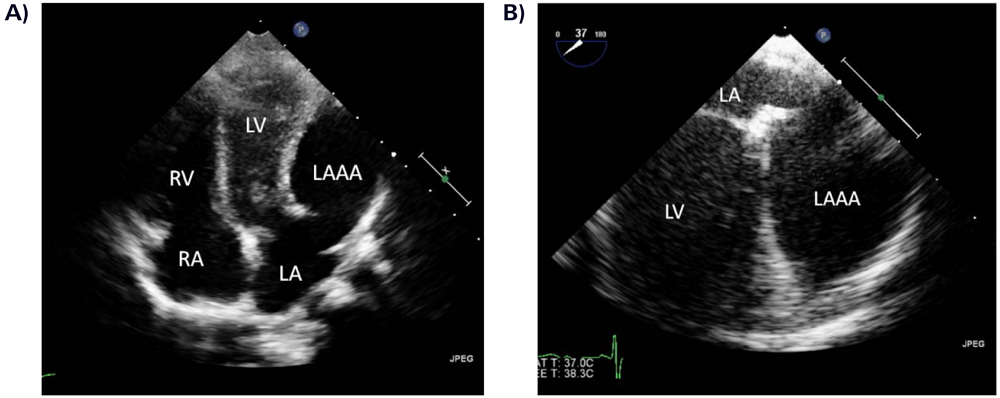

無症候性左心耳瘤の病理組織学的検討Histopathological Findings of Asymptomatic Left Atrial Appendage Aneurysm